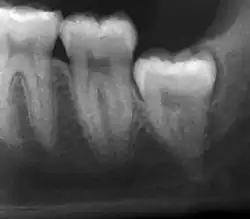

El diagnóstico de impactación se puede hacer clínicamente si es visible una parte suficiente de la muela del juicio para determinar su angulación y profundidad, y si el paciente es lo suficientemente mayor como para que sea improbable una erupción o enderezamiento posterior. Las muelas del juicio continúan moviéndose hasta la edad de 25 años debido a la erupción, y luego continúan algún movimiento posterior debido a la enfermedad periodontal.[18]

Si el diente no se puede evaluar únicamente con el examen clínico, el diagnóstico se realiza mediante una radiografía panorámica o una tomografía computarizada de haz cónico. Cuando las muelas del juicio no erupcionadas todavía tienen potencial de erupción, se utilizan varios factores predictivos para determinar la probabilidad de que los dientes se impacten. La relación de espacio entre la longitud de la corona del diente y la cantidad de espacio disponible, el ángulo de los dientes en comparación con los otros dientes son los dos predictores más utilizados, siendo la relación de espacio la más precisa. A pesar de la capacidad de movimiento en la edad adulta temprana, la probabilidad de que el diente se impacte puede predecirse cuando la relación entre el espacio disponible y la longitud de la corona del diente es inferior a 1.:[5] 141